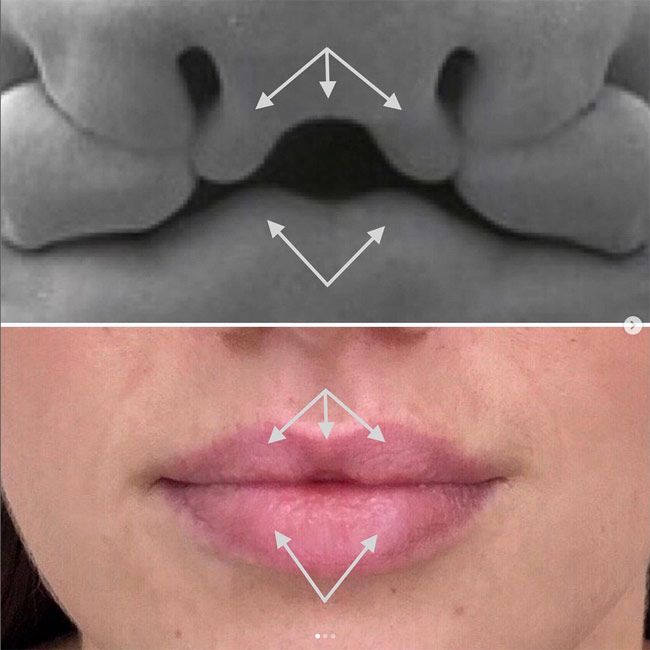

Pacjentka wraca po modelowaniu ust i mówi, że coś jej się nie zgadza. Patrzysz - i faktycznie widzisz asymetrię. Pierwsza myśl? Coś poszło nie tak. Pokażemy Ci jeden przypadek z gabinetu, który dobrze pokazuje, jak łatwo o błędne wnioski.

Do gabinetu zgłosiła się pacjentka około 45 roku życia, która oczekiwała efektu lekkiego nawilżenia i wyrównania asymetrii ust.

Zabieg przebiegł bezproblemowo. Efekt był zgodny z oczekiwaniami. Pani zgłosiła się 3 tygodnie po zabiegu, ponieważ usta po modelowaniu jej się podobały, ale…

Jej uwagę przyciągnął środek dolnej wargi - niewielkie zagłębienie, które zaczęła odbierać jako coś nieprawidłowego.

Pierwszy odruch w takiej sytuacji jest dość oczywisty - szukamy miejsca do korekty. Tylko że tutaj rozwiązanie było dużo prostsze. Wystarczyło wrócić do zdjęć sprzed zabiegu. Dopiero wtedy było widać, że:

- to wgłobienie było obecne już wcześniej

- po zabiegu nie powstało nic nowego

- zmieniła się jedynie jego widoczność

To co widzicie najłatwiej będzie wyjaśnić przemycając szybką lekcję anatomii i embriologii. W miarę rozwoju naszych twarzy, formuje się seria wyrostków (processes) (nosowe, szczękowe i żuchwowe), które łączą się w linii środkowej, tworząc ciągłą centralną strukturę, której pozostałością są guzki.

U niektórych osób miejsce połączenia się guzków nie jest widoczne, jednak u innych może być bardzo wyraźne.

No dobra, to co właściwie się tu wydarzyło? Kwas zrobił swoje - rozłożył się tam, gdzie tkanki były bardziej “podatne”, czyli głównie po bokach. A środek? Środek został.

Dlaczego? Bo to miejsce zachowuje się trochę jak mini blizna - jest mniej elastyczne i nie rozciąga się tak jak reszta wargi. Więc preparat go po prostu nie “wypełnił”. Powstał efekt, który pacjentka odebrała jako asymetrię - boki się wypełniły, środek został taki jak wcześniej, tylko zaczął być bardziej widoczny.

Dopiero kiedy pokazałyśmy jej zdjęcia sprzed zabiegu, wszystko stało się oczywiste. Zobaczyła, że to wgłobienie było tam od zawsze - tylko wcześniej nikt nie zwracał na nie uwagi. Na koniec wizyty śmiała się, że przez całe życie nie wiedziała, że ma tam jakąkolwiek “bliznę”.